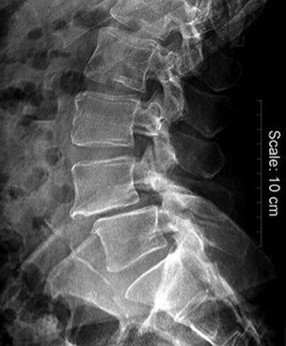

A 40-year-old male presents with severe mechanical back pain. Standing lateral radiographs reveal an isthmic spondylolisthesis at L5-S1. The L5 vertebral body has slipped anteriorly by 60% of the width of the S1 endplate. According to the Meyerding classification, what grade is this slip?